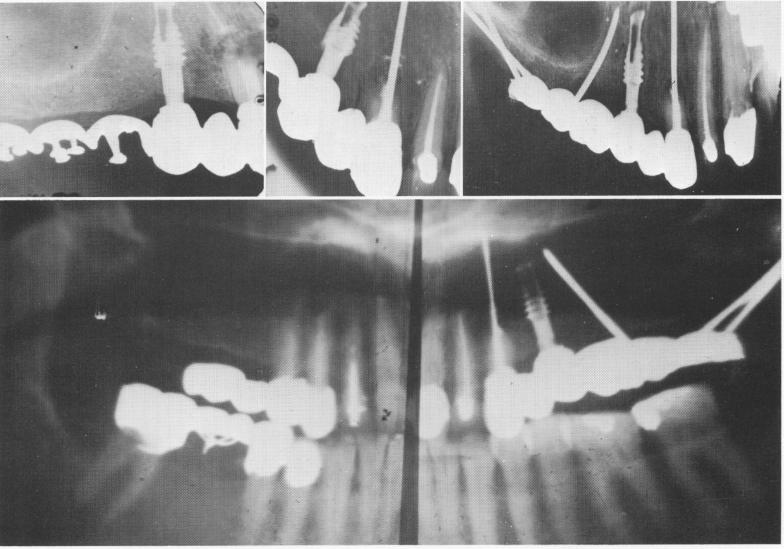

Fig. 13-56. A, Roentgenogram shows broken cuspid root prior to its removal. The vent-plant is seen in the bicuspid region. B, The endodontic implant stabilizer as seen 6 months after apicoectomy. C, A cross-sectional occlusal x-ray taken 2 years after initial insertions shows the endodontic implant stabilizer, the vent-plant, and the triplant. Notice the regeneration of bone resembling a lamina dura around the mesial wall of the vent plant and the circumvention of the sinus with the triplant. D, A Panorex x-ray illustrating the bridge and implants 5 years postoperatively.

1 Endodontic implant stabilizer seen six months after apicoectomy

2 Occlusal x ray shows endodontic implant stabilizer,ventplant & triplant